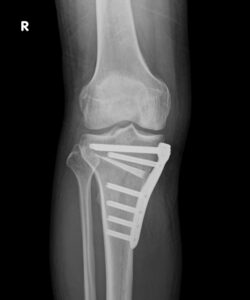

<膝周囲骨切り術>

変形性膝関節症や、骨壊死、半月板損傷を発症していて、下肢のアラインメント(体重のかかる中心軸)が不良な場合には、膝周囲の骨切り術を実施してアラインメントを矯正する手術を推奨します。半月板損傷がある場合には、骨切り術と半月板手術を併施することで効果が格段に上がります。この手術は人工関節とは異なり、膝関節自体は温存する手術なので、術後もスポーツを続けたい方や人工関節を受けるにはまだ年齢が若いという方に向いています。逆に、高度変形、肥満、可動域の悪い方、高齢者、骨粗鬆症患者、喫煙者は成績不良という報告があり、適応外となることがあります。骨切り術の方法は、変形の程度や方向に応じて複数ありますので、どの術式が最適かは担当医にご相談ください。